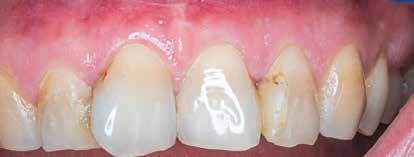

A gyökértömés elkészítése során meleg vertikális kompakciós technikát alkalmaztunk, sealerként pedig CeraSeal-t (Meta Biomed; 3. ábra) használtunk. A reszorbciós üreget Biodentine-nel (Septodont; 4. a–b ábra) töltöttük fel. A reszorbcióval érintett területtől koronális irányba elhelyezkedő csatornaszakaszt pedig tisztán meleg guttaperchával kezeltük. Ezt követően a lebenyszéleket visszafektettük, és varratok behelyezésével eredeti pozíciójuknak megfelelően rögzítettük. A koronai részt kompozit tömőanyag segítségével állítottuk helyre. Kontrollvizsgálatra 5, illetve 30 hónappal később került sor (5. ábra). A csontos telődés jelei már 5 hónap után észlelhetők voltak (6. a–c ábra). A 30 hónappal később végzett kontroll során sem találtunk csontban lévő lézióra, törésre vagy egyéb pathológiás elváltozásra utaló jeleket (7. a–b ábra)

MTA-val (Mineral Trioxide Aggregate; Harvard Dental) töltöttük fel. A léziótól koronális irányban elhelyezkedő gyökércsatorna-szakaszt meleg guttaperchával zártuk, majd az MTA-val kitöltött üregre egy kis darab kollagénszivacsot helyeztünk és a lebenyt varratok segítségével eredeti pozíciójában rögzítettük (12. a–b; 13. a–b. ábra). A fog koronai részét Gradia kompozit tömőanyaggal állítottuk helyre (GC; 14. a–b; 15. ábra). Kontrollvizsgálatra két (16. a–b ábra) és négy évvel (17. a–b ábra) később került sor. A kontrollfelvételeken a bukkális kortikális jelenléte volt észlelhető. A fog körüli parodoncium egészséges volt, valamint a páciens sem számolt be tünetekről.

13. a–c ábra: A reszorbtív üreg bioanyaggal való feltöltése és a kollagénszivacs elhelyezése. – 14. a–b ábra: Posztoperatív röntgen (a), a varratok behelyezését követően látható klinikai helyzet (b).

15. ábra: A 14 nappal később látható állapot.